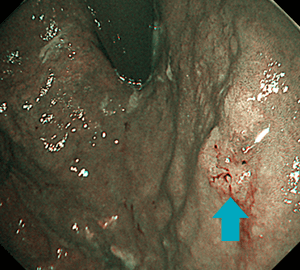

NBIによる血管および表面構造の明瞭化

がん細胞は血管から栄養されて急速に増殖するため、がん部には細い血管が密に集まっていることが多くなっています。NBIはこの小さな異常血管を発見するのに大変有用で、がんの描出・詳細観察にあたって有効な手段といえます。またがん以外の病変においても多くの場合で周囲粘膜とのコントラストが上昇するため、それら病変の発見・観察にあたってもその力を発揮します。

胃体上部の淡い褪色調の早期胃がん病変ですが…

NBI観察で明瞭化します。